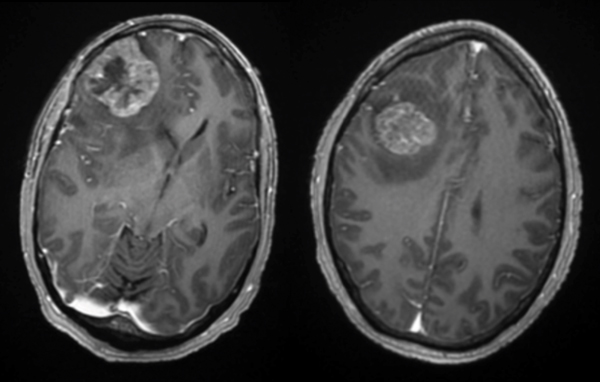

Pre-op

This is a 56-year-old man with a history of COPD and asthma who presented with a syncopal event and one week of retro-orbital headaches, blurry vision, and personality changes including apathy and disinhibition. He had a 40- pack-year smoking history but no prior malignancy. The exam revealed a pronator dri on the le upper extremity. MRI brain demonstrated 2 large right frontal heterogeneously enhancing masses with vasogenic edema causing midline shi and subfalcine herniation. The largest lesion was 3.9 x 4.0 cm on the inferior/sub frontal cortical surface, while the other was 3.0 x 2.7 cm in the superior subcortical frontal lobe. Further imaging showed a mediastinal mass suspicious for malignancy. He was started on Decadron for edema and Keppra for seizure prophylaxis.